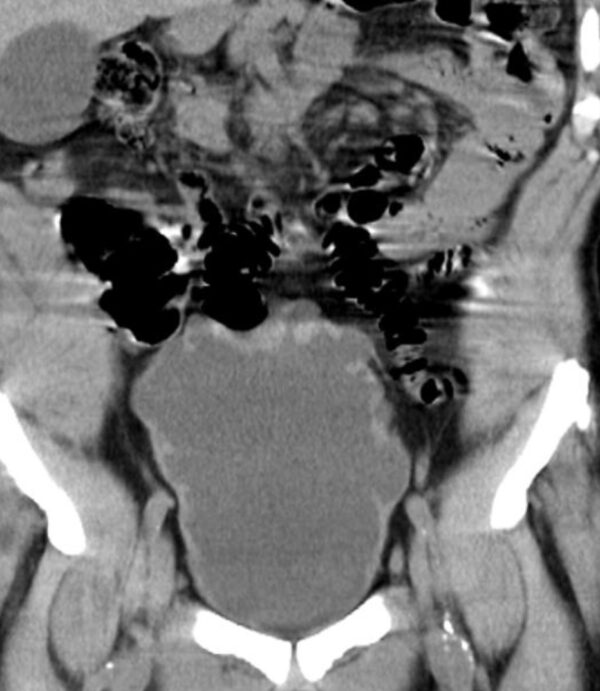

https://radiopaedia.org/cases/neurogenic-bladder-ct-findings-christmas-tree-bladder?lang=us

| Modality | CT |

| Region | GUT |